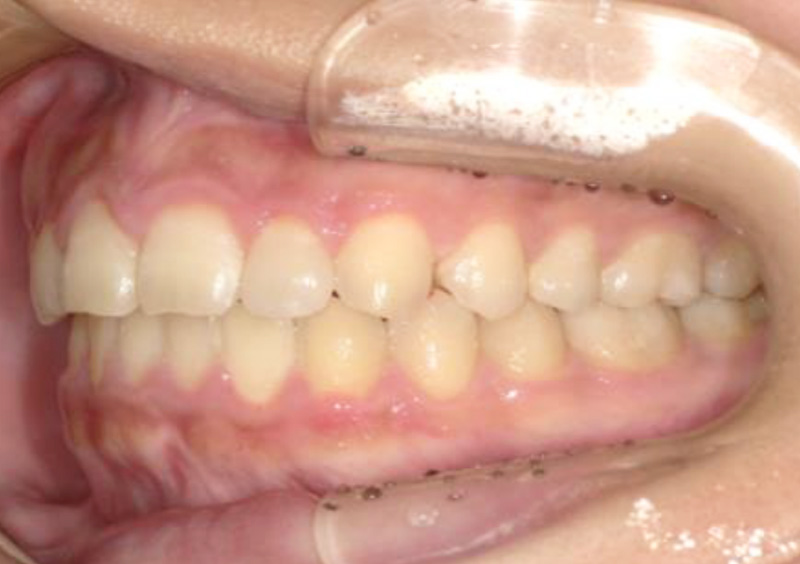

大人の矯正治療 歯に隙間がある(空隙歯列) 2025.10.24 【マルチブラケット矯正】隙間が気になる 治療前 治療後 担当医 一瀬 悠依華 先生 主訴 隙間が気になる。 期間 2年半 費用 65万円 治療内容 マルチブラケット装置 治療に伴うリスク 歯根吸収、歯肉退縮 関連症例